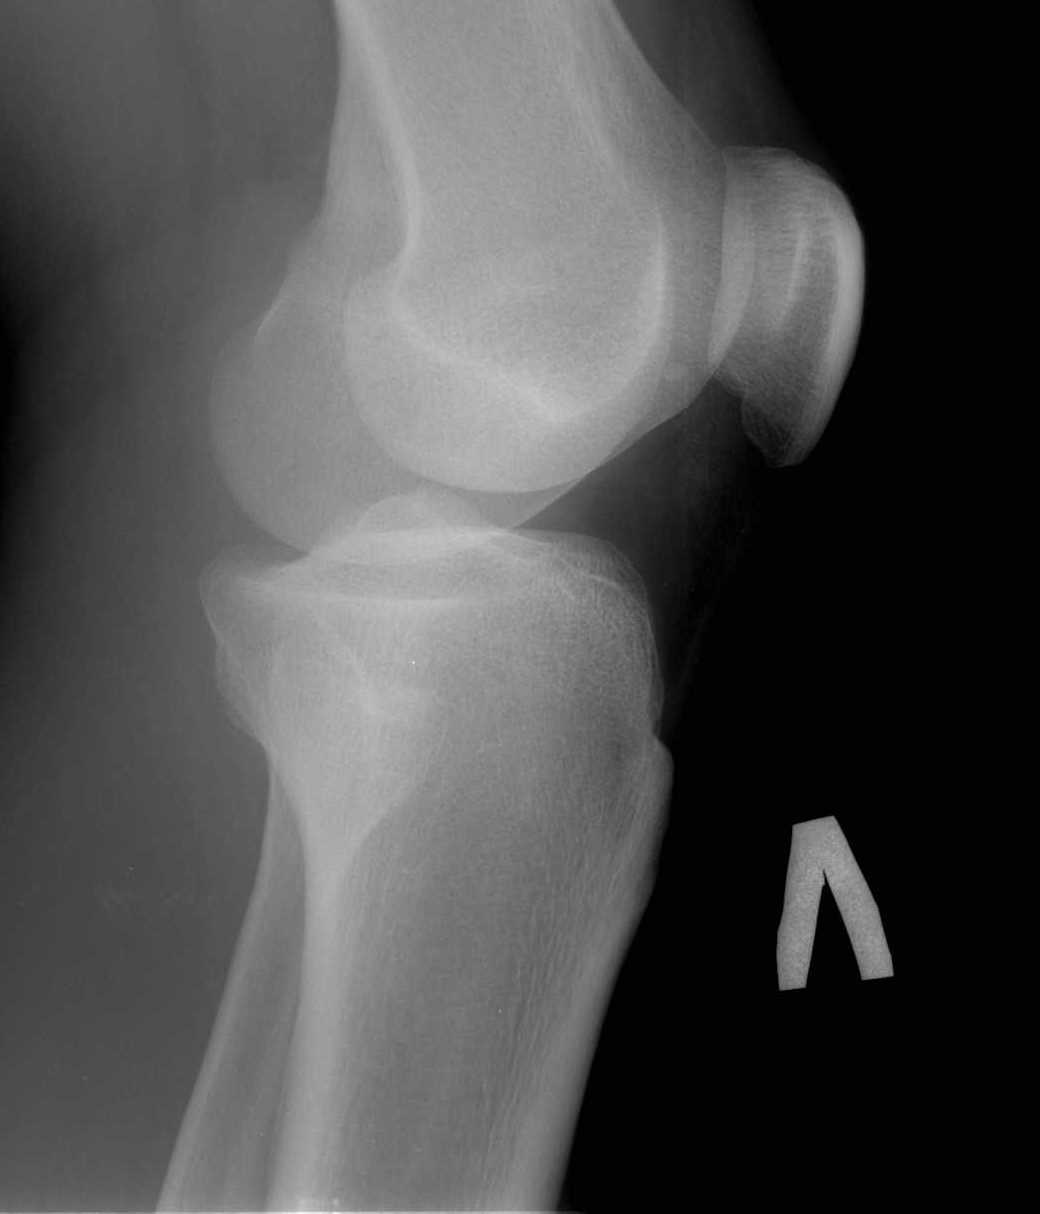

Добрый вечер уважаемые колеги. Проблема в следующем.Обратился пациент, возраст 26лет.

Травму левого коленного сустава отмечает около 2-х месяцев назад( при игре в футбол). За мед

помощью обратился не сразу, а как обратился, все консервативные мероприятия( мази, гели,

мумие, физиолечение) без эффекта. Сохраняются боли при нагрузке. Локально: отека

коленного сустава нет, выпота в суставе нет(и не было). Связочный аппарат коленного сустава

стабилен. Симптомы повреждения внутрисуставных структур отр(-). Пальпаторно умеренная

болезненность в проекции головки м/берцовой кости, а при сравнительном исследовании

определяется подвижность головки м/берцовой кости по отношению к тибии с больной

стороны.Ds: Застарелый разрыв проксимального межберцового синдесмоза левой